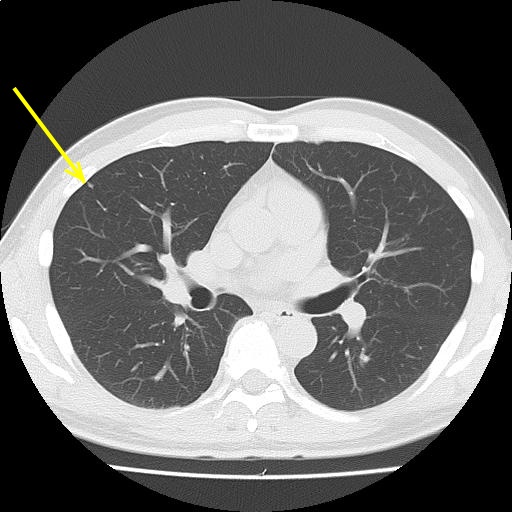

CTスライス画像

(Findings)

両肺末梢に微小結節を散見し、陳旧性炎症性変化と考える。

縦隔リンパ節腫大を認めない。胸水を認めない。